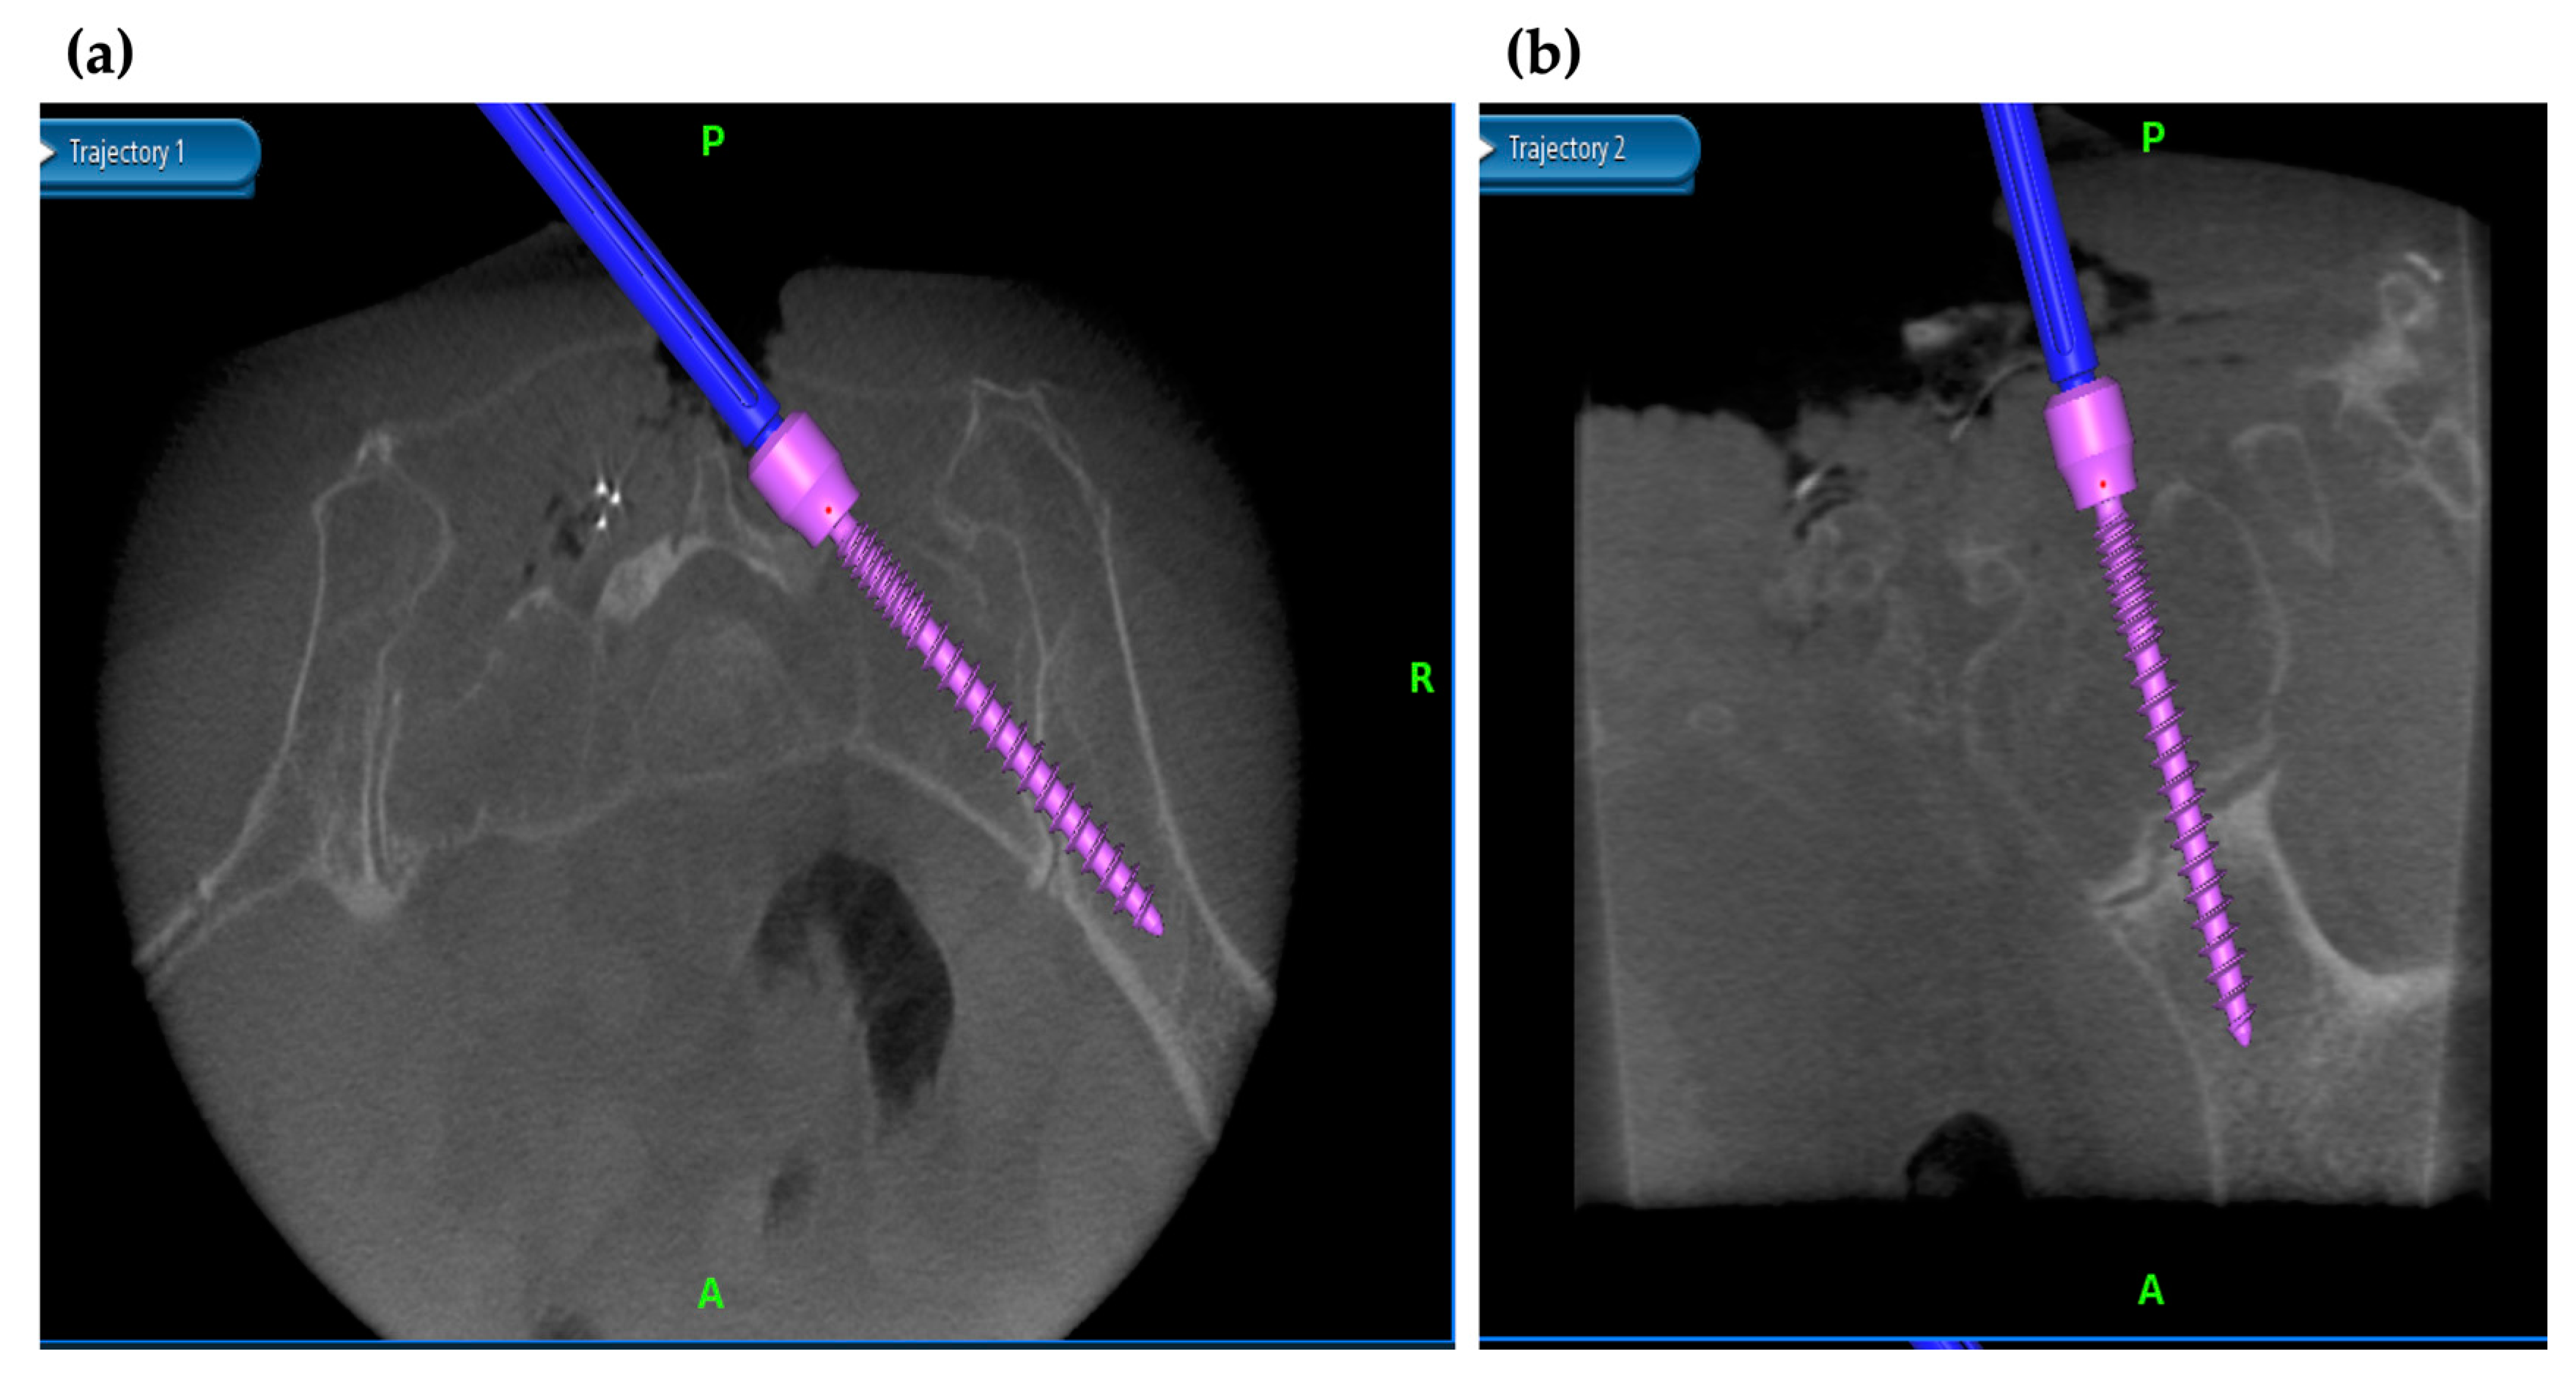

3.5. Application of Navigation System in MISt Procedures

3.6. Robotics-Assisted Surgery